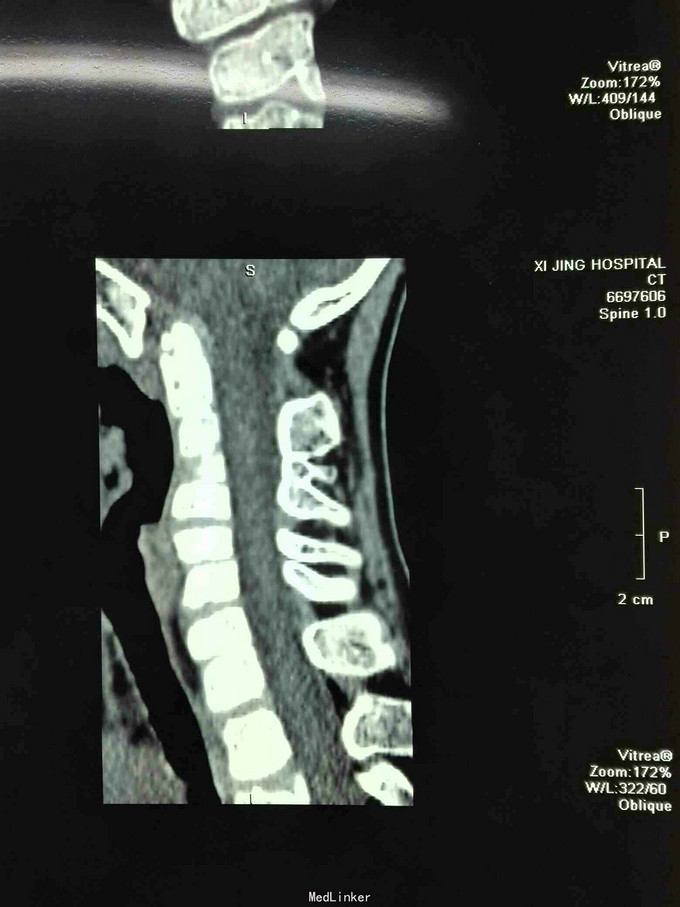

先天脊柱畸形

先天脊柱畸形8年。